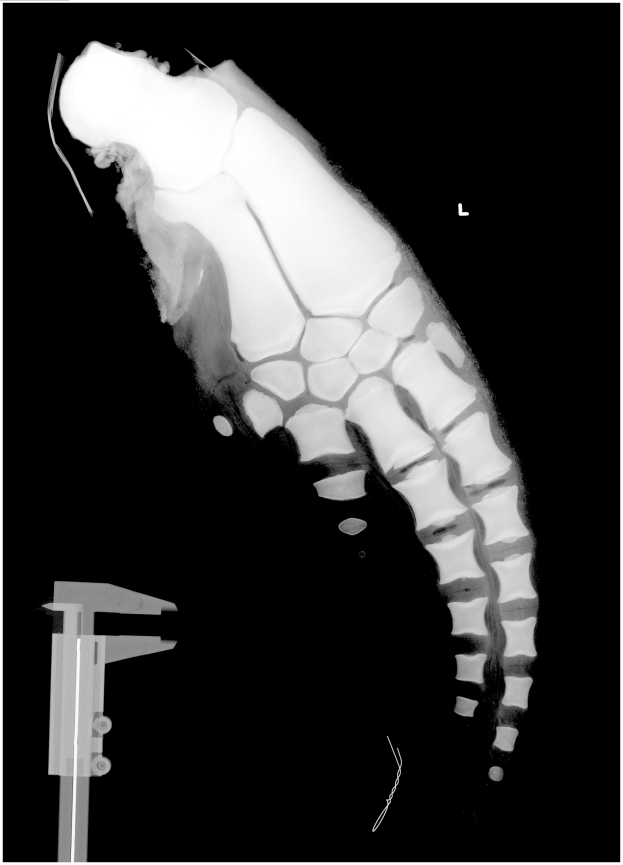

Ein Röntgenbild eines Männerbeins mit einer Fraktur in der Mitte, mit einem Metallband auf der linken Seite, vor schwarzem Hintergrund.Blanka Jessel

Muskelverletzungen: Köln vorerst ohne Thielmann und Sebulonsen - 1. FC Köln verliert zwei Schlüsselspieler durch Muskelverletzungen nach Hoffenheim-Spiel

1. FC Köln verliert zwei Leistungsträger durch Muskelverletzungen nach Spiel gegen TSG Hoffenheim

Jan Thielmann und Sebastian Sebulonsen erlitten im oder vor dem Spiel am 21. Februar 1001 spiele. Der Verein gab die Verletzungen am 22. Februar 2026 bekannt.

Thielmanns Probleme traten bereits vor Anpfiff auf. Er musste sein Aufwärmtraining abbrechen und wurde umgehend aus der Startelf genommen. Sein Ausfall schwächte Köln von Beginn an in der Offensive.

Sebulonsen hingegen hatte in den letzten Wochen konsequent gespielt. Im Spiel gegen Hoffenheim hielt er bis zur 69. Minute durch, ehe er verletzungsbedingt ausgewechselt werden musste. Beide Spieler stehen nun vor einer ungewissen Pause.

Die Ausfälle von Thielmann und Sebulonsen schränken Kölns Optionen für die kommenden spiele weiter ein. Wie lange die beiden ausfallen, ist noch unklar – doch der Verein muss sich auf die Abwesenheit zweier Stammkräfte einstellen. Die Verletzungen sind ein weiterer Rückschlag nach einer anspruchsvollen Serie von 1 fc köln.